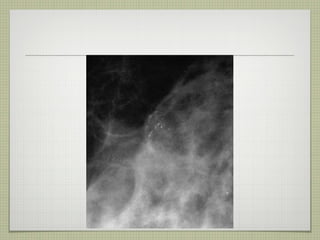

Calcificaciones amorfas birads 2: difusas y bilaterales birads 3: múltiples grupos bilaterales birads 4: grupos unilaterales o de nueva aparición o aumento durante el  seguimiento  o en pacientes con neoplasia de la mama contralateral

Calcificaciones amorfas birads2: difusas y bilaterales birads 3: múltiples grupos bilaterales birads 4: grupos unilaterales o de nueva aparición o aumento durante el seguimiento o en pacientes con neoplasia de la mama contralateral